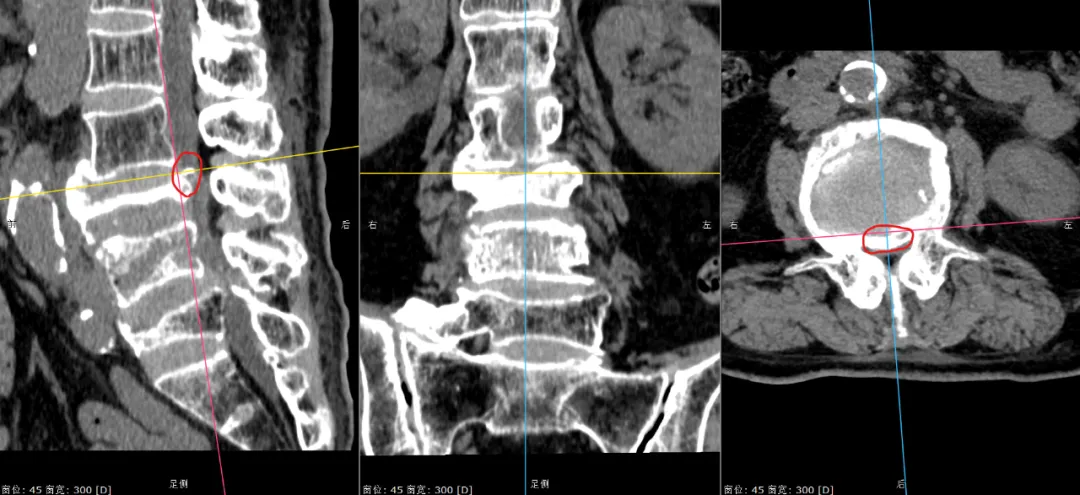

▲張奶奶的三處腰椎骨折(標紅處為骨折內巨大空腔、標綠處為陳舊性骨折、標黃處為受壓到極限的馬尾神經)。

▲張奶奶的神經受壓處1(紅圈內為壓迫神經的骨塊)。